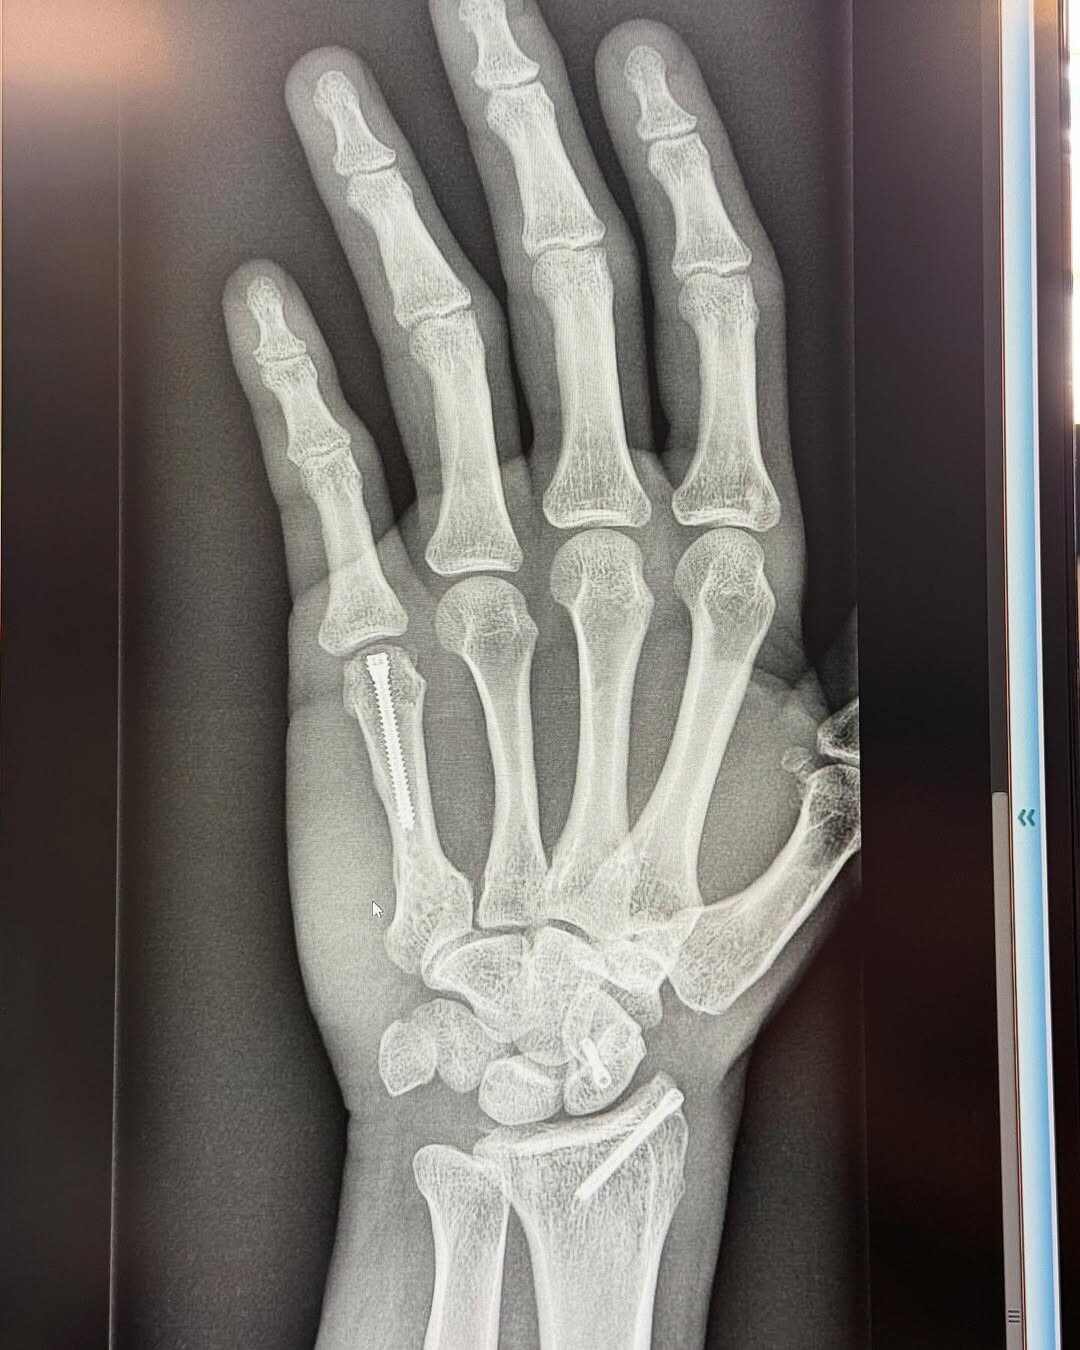

Il campione in carica della classe regina è inciampato in una brutta caduta nel primo giorno di test